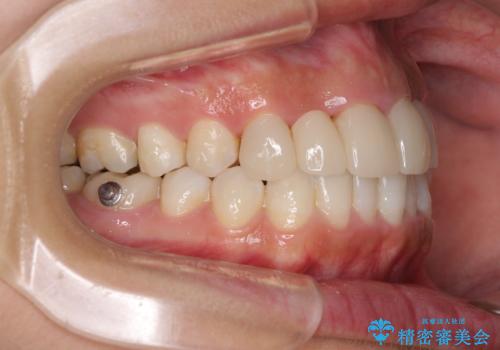

- 審美的ではない上の前歯とデコボコの下の前歯、歯茎が腫れている奥歯を気にして来院された患者様です。

根管治療の必要な歯がいくつかあるため、まずは根管治療を行い、その後インビザラインにて矯正治療を行うこととしました。

矯正治療後に前歯をセラミックブリッジに、奥の銀歯はセラミックインレーやPGAインレー(ゴールドインレー)にて補綴・修復治療を行うこととしました。

矯正治療により下顎前歯を整列させたため、上顎前歯のセラミックブリッジを補綴することで口元を少し下げることができました。

ヒトの目線がいつも口元に向けられているように感じることがなくなり、患者様には大変満足していただきました。